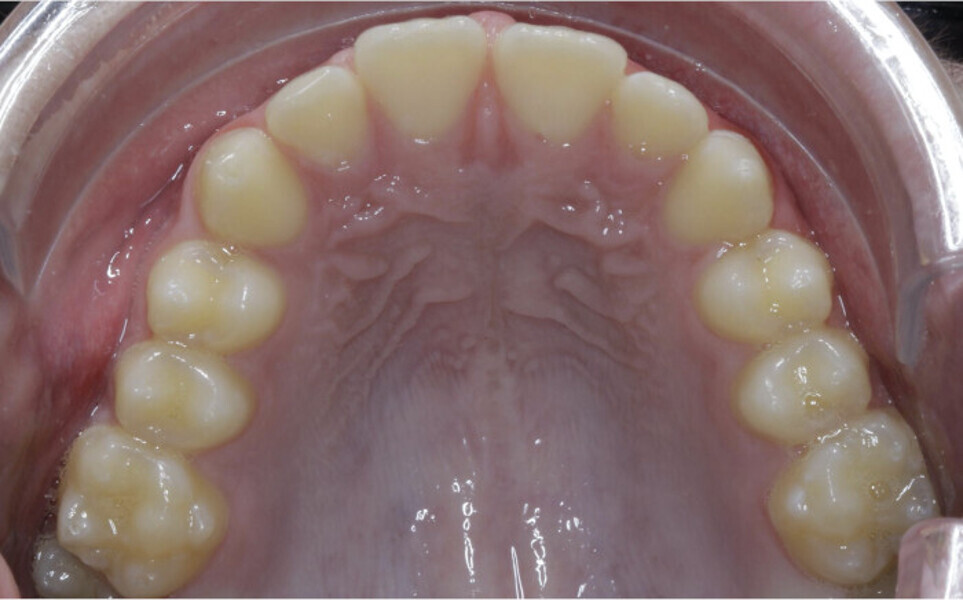

New Age orthodontics and orthopaedics with temporary anchorage devices